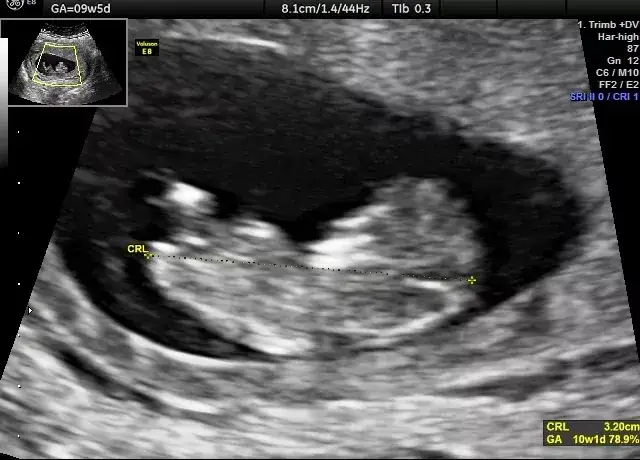

Wczesne USG, wykonywane zazwyczaj między 6. a 10. tygodniem ciąży, choć nieobowiązkowe, jest bardzo pomocne i często rekomendowane. Podczas tego badania lekarz ocenia kilka kluczowych aspektów:

- Uwidocznienie pęcherzyka ciążowego i zarodka.

- Stwierdzenie akcji serca płodu.

- Wstępna ocena wieku ciążowego na podstawie pomiaru CRL.

Zazwyczaj bicie serca płodu można zobaczyć w USG dopochwowym około 6. tygodnia ciąży. Jego obecność jest dla nas, lekarzy, najważniejszym potwierdzeniem żywotności ciąży. To moment, który często przynosi ogromną ulgę i radość przyszłym rodzicom.

Na wczesnym etapie ciąży możemy również ocenić liczbę zarodków, co pozwala na wczesne wykrycie ciąży mnogiej. To istotna informacja, która wpływa na dalsze planowanie opieki.